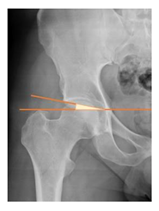

Plain radiographs were evaluated preoperatively and at the most recent follow-up, after appropriate calibration. Positional parameters were assessed according to values guidelines from published literature, as listed in Table 1 [23,24,25,26,27,28,29,30,31]. Femoral stem and acetabular cup osteointegration were quantified according to Engh [32] and Moore scale [33]. Heterotopic ossifications were graded according to the Brooker system [34].

3.4. Radiographic Evaluation

Preoperative and postoperative radiographic data are reported in Table 4. Preoperatively, 18 THR (24.3%) were implanted in skeletally immature children with closed triradiate cartilage (1 ≤ Risser ≤ 3). Radiographic acetabular insufficiency (LCEA < 25° and AI > 13°) was detected in 14 hips (18.9%), while protrusion was present in 3 hips (4.1%) An excessive valgus of the femoral neck was observed in 19 hips (25.7%), while an important varus deformity was present in 7 hips (9.5%).

Postoperative radiographs showed a significant vertical malposition of the cup in 1 case (1.4%), a significant varus stem in 8 cases (10.8%) and a significant valgus stem in 1 case (1.4%). Two patients (2.7%) showed moderate heterotopic bone formation (Brooker ≥ 2), that did not significantly affect the hip motion and symptoms. All those THR that did not undergo revision showed good radiographic osteointegration, with no evidence of implant breakage, radiographic lucencies, bone defects, cup migration, or stem subsidence at the most recent radiographs.